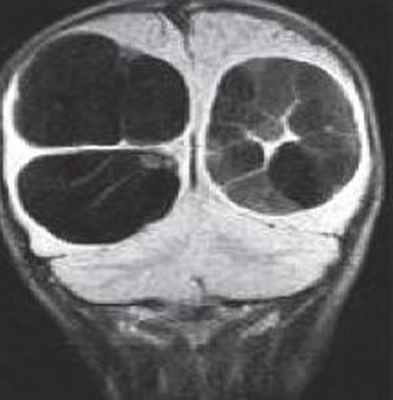

Нейроглиальные (нейроэпителиальные) кисты – врождённые кисты различной этиологии, локализующиеся в паренхиме мозга или в области сосудистого сплетения желудочков. Обычно округлые, с гладкими стенками. Очень часто такие кисты сочетаются с аномалиями развития: отсутствием прозрачной перегородки и полимикрогирией. При МРТ головного мозга содержимое кист ликворное, иногда с небольшой примесью белка.

Кисты средней линии – киста прозрачной перегородки (cavum septi pellucidi), полость Верге (cavum Vergae) и киста промежуточного паруса (cavum veli interpositi) – являются нормальными структурами головного мозга плода. В течение 6 месяцев после рождения у большинства людей они запустевают, но могут и сохраниться, визуализируясь при этом на МРТ головного мозга. По-видимому, эти полости не имеют клинического значения и относятся к случайным находкам при томографии. Киста прозрачной перегородки (еще называют V желудочком) является медиальной стенкой боковых желудочков и ограничена спереди коленом мозолистого тела, сверху мозолистым телом и сзади столбами свода . Полость Верге представляет собой продолжение кисты прозрачной перегородки кзади и расположена между телами желудочков . Обычно обе кисты сочетаются. Киста промежуточного паруса расположена в крыше III желудочка (tela choroidea), между треугольниками боковых желудочков на уровне отверстий Монро. Она ограничена сверху мозолистым телом, cзади цистерной четверохолмия и снизу III желудочком.

МРТ головного мозга. Корональная Т1-взвешенная МРТ. Многокамерные эхинококковые кисты.